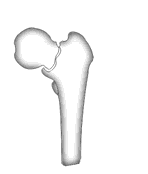

А что насчет остеостомии типа как на картинке в приложении?

Красивая картинка !

Вчера сделали остеотомию, делали близко к тому, как на той картинке.

Картинка тут.

То, что получилось, в приложении (без такой красивой анимации, к сожалению